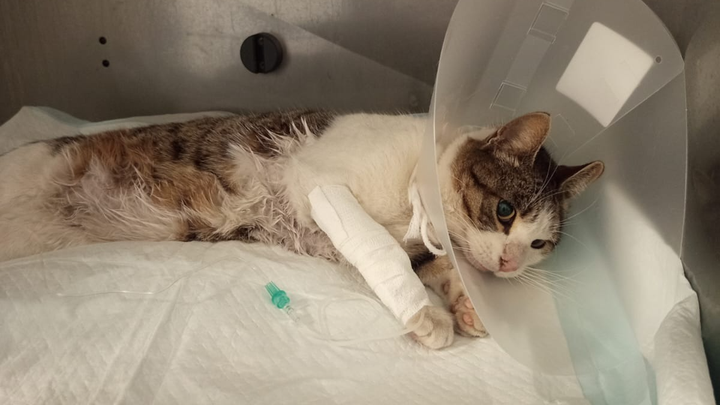

Il 6 gennaio riceviamo una chiamata dal signor Vincenzo Maniscalco: nel suo orto c’è un gatto che si trascina sul posteriore, incapace di camminare.

Quando arriviamo, Felice – perché così lo chiameremo – è nascosto in un ripostiglio, tremante, raggomitolato come un animale che ha smesso di credere nella bontà del mondo.

Ci vogliono più di due ore per prenderlo. Non fugge da noi: fugge dal dolore che qualcuno gli ha inflitto.

Al pronto soccorso veterinario di Milano, le radiografie parlano chiaro:

Felice ha un bossolo di proiettile vicino alla spina dorsale.

Un proiettile che è dentro di lui da tempo, perché le ferite esterne sono ormai cicatrizzate.

Qualcuno gli ha sparato.

Qualcuno ha preso la mira, ha premuto il grilletto e poi lo ha lasciato lì, a soffrire in silenzio.

Lo trasferiamo in un’altra clinica per una Risonanza Magnetica e ulteriori indagini.

Felice è affetto da FIP secca neurologica.

Da quel momento è seguito dal reparto di Neurologia, con cure continue e delicate.

E lui… lui reagisce.

Reagisce ai farmaci, reagisce alle terapie, reagisce alla vita.

E oggi, con nostra enorme emozione, Felice ha iniziato a mostrare reazioni agli arti inferiori.

Piccoli movimenti, piccoli segnali… ma per ora ci sono.

E per un gatto che non sentiva più nulla, è un miracolo.